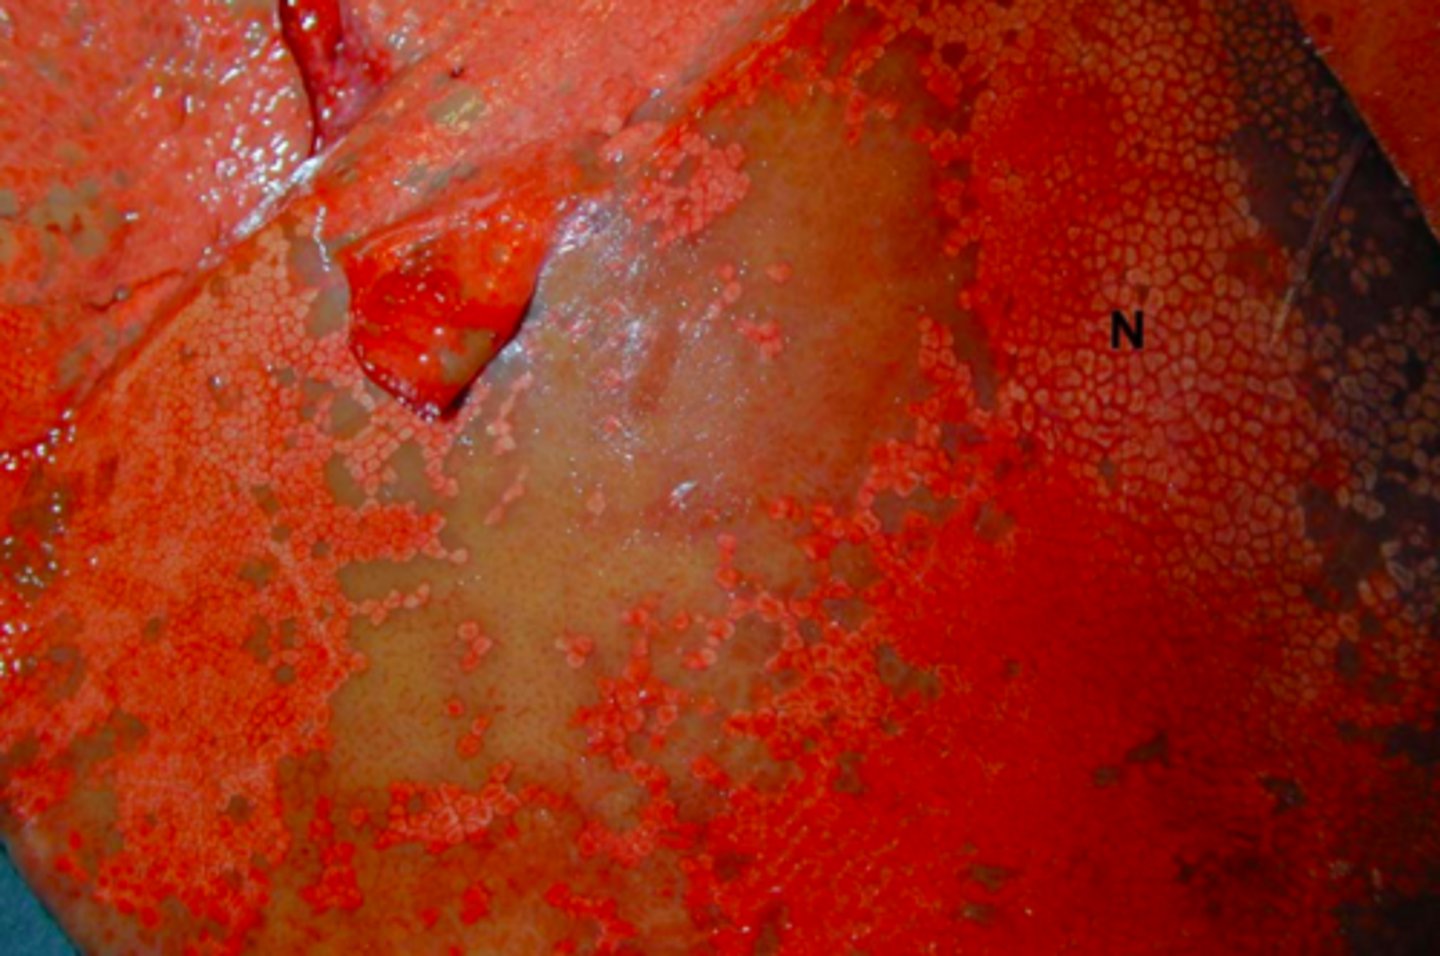

Akut dissemineret nekrose

vævet er tørt

Typisk hæmatogen spredning

Lever fra okse, hvad er den patoanatomiske diagnose?